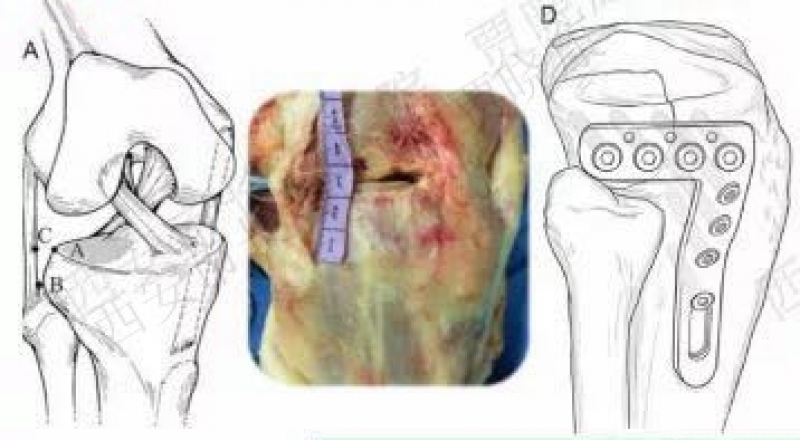

一、胫骨平台后外侧解剖

二、后外侧切口介绍

1. 腓骨头截骨

2010年

2008年禹宝庆

适用于41B2.1x或u并t,41B3.1x或u并t。

4.股骨外髁截骨入路

2014年

采用垂直前外侧切口。